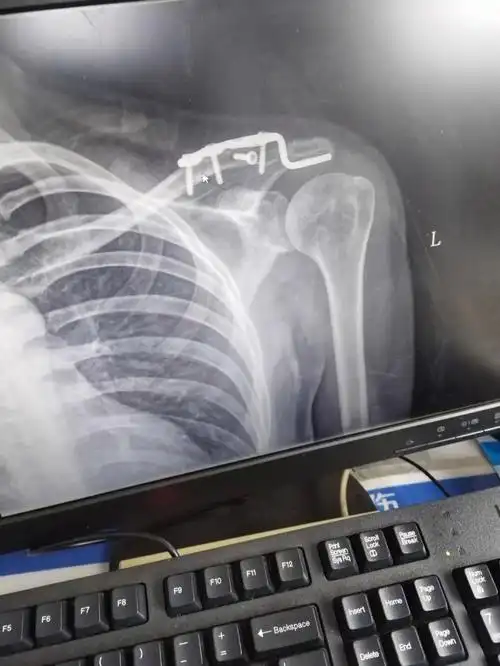

锁骨骨折恢复日记